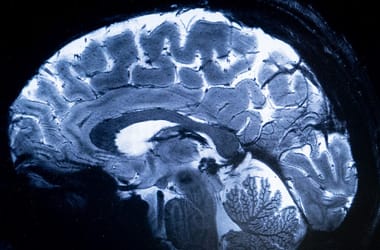

Ha kognitív erőforrásokat igénylő feladatokat kell végezni, többet dolgozik az obszesszív-kompulzív zavarral élők agya, mint egészséges társaikéé – állapította meg nemrég egy amerikai kutatás, amely MR-rel vizsgálta a kényszerbetegek agyát.